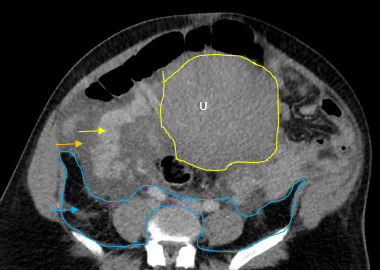

The initial impressions of the axial and coronal CT images revealed dilation of the right ovarian vein in addition to intraperitoneal fluid accumulation on the right side (Fig. 1-2). Portovenous and delayed phase images did not demonstrate contrast pooling or persistent hyperattenuation to suggest hyperacute hemorrhage (Fig. 3-4). Additionally, there was evidence of peritoneal air present between the uterine myometrium and ovarian vasculature most notable along the right aspect of the anterior inferior uterus. A contour abnormality along the right parasagittal lower uterine segment was also noted and interpreted as a uterine defect without signs of free intraperitoneal hemorrhage. In conjunction with her clinical picture, these radiologic findings raised our suspicion for a contained uterine rupture although there were no pathognomonic imaging findings to confirm an associated retroperitoneal hematoma. The patient was urgently taken to the operating room for an exploratory laparotomy to confirm the diagnosis and to manage surgically if indicated.

There was no evidence of hemoperitoneum upon abdominal entry. There was a minor 1 cm x 1 cm superficial serosal defect noted at the right cornua, which was hemostatic and secondary to manipulation of the uterus. Most notably, a large non-expanding right-sided broad ligament hematoma measuring 15 cm x 6 cm was noted extending into the retroperitoneal space over the site of suspected uterine rupture (Fig. 5-7). The patient remained hemodynamically stable intraoperatively, and following direct observation, the hematoma was noted to be non-expanding. The uterus was taken off tension, and the decision was made to close the patient without further intervention.

Uterine rupture was highly suspected even prior to the exploratory laparotomy due to the presence of air between the uterine myometrium and the ovarian vessels. Figures 1-4 describe CT findings consistent with uterine rupture. This is the first case report of a uterine rupture being managed conservatively similarly to previously described management options for contained uterine hematomas.